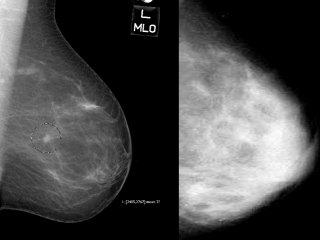

On the left is a mammogram of a fatty breast.

Since fat is radiolucent it produces a dark background which makes the

small, white stellate tumour in the center of the breast relatively easy to

see. The mammogram on the right shows a very dense breast. It too has a

cancer in roughly the same location but I challenge you to find it.